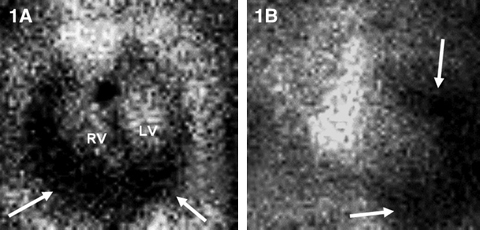

On the GHPS (Figure 1) a radiolucent pericardial halo was apparent, raising concerns for pericardial effusion. The rest of the study was unremarkable, with normal regional wall motion and quantitative ejection fraction of the cardiac ventricles. Comparison with a recent chest x-ray (Figure 2) revealed radiolucency external to the chest wall. Subsequent transthoracic echocardiography (Figure 3) ruled out the presence of pericardial effusion.

1: GHPS left anterior oblique 45° (1A) and anterior (1B) views. Pericardial halo suggestive of pericardial effusion (arrows). |